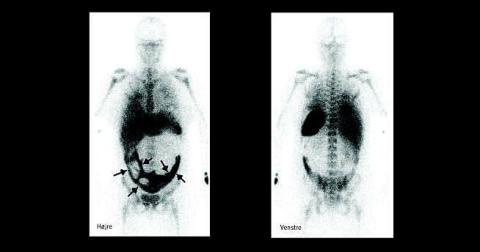

Der blev udført abrasio på mistanke om focus i uterus, men uden bedring i patientens tilstand. En akut leukocytscintigrafi med 99m Tc-mærkede leukocytter viste opladning i et velafgrænset område i nedre abdomen og flere hot spots . Patologisk akkumulation af leukocytter i dette område blev tolket som infektion i parametriet.